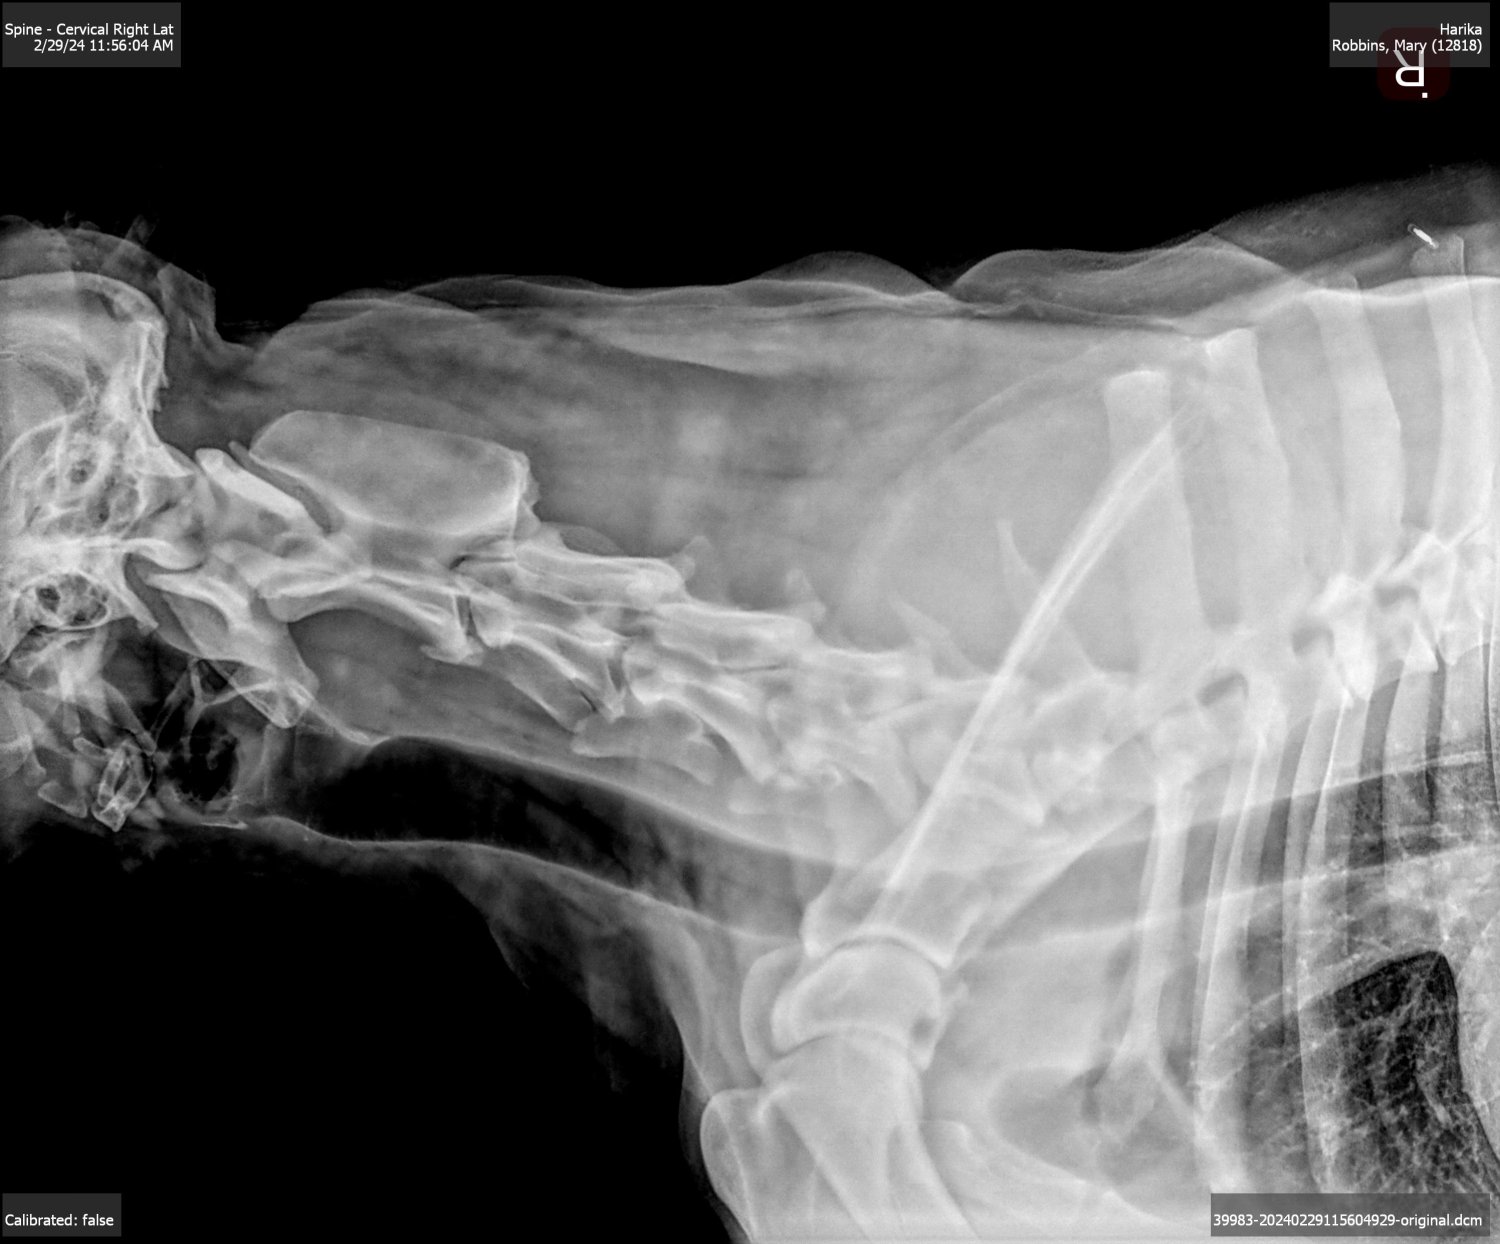

Here are the x-rays. From shoulders to base of skull disc spaces narrow significantly until neck. There are no spaces between discs in upper neck and about 6" nearest head looks like one solidified bone. Not sure if I can post x-rays but will try. I am going by x-rays of my back before surgery L4-L5. In order from head to tail then shoulder x-rays. I am not a vet so maybe someone can read them better than me. X-ray of neck nearest skull seems to show top of spine is solid - bone or arthritis?

Looking at #4 - spine nearest tail shows normal spaces between spinal processes (discs) with some sharp areas possibly inferring bone spurs according to what vet told DS1 when he picked her up. Spaces progressively get narrower as you go backwards to #1 x-ray showing neck discs bone on bone. According to what the vet told DS1, the discs in the area of the shoulder are badly compressed showing permanent damage.